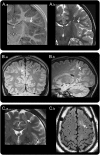

Methods: Retrospective review of clinical records, EEG, MRI, and histopathology in 32 patients with drug-resistant epilepsy and MRI-positive (72% 3.0 tesla), pathologically proven (type 2B cortical dysplasia) BOSDs operated at our centers during 2005-2013.

Results: Localization of BOSDs was frontal in 19, insula in 5, parietal in 5, and temporal in 3, on the convexity or interhemispheric surfaces. BOSDs were missed on initial MRI at our centers in 22% of patients. Patients presented with focal seizures during infancy in 9, preschool years in 15, and school years in 8 (median age 5 years). Seizures were stereotyped, predominantly nocturnal, and typically nonconvulsive, with semiology referable to the fronto-central or perisylvian regions. Seizures occurred at high frequency during active periods, but often went into prolonged remission with carbamazepine or phenytoin. Intellect was normal or borderline, except in patients with seizure onset during infancy. Scalp EEG frequently revealed localized interictal epileptiform discharges and ictal rhythms. Patients underwent lesionectomy (median age 14 years) guided by electrocorticography and MRI, with prior intracranial EEG monitoring in only one patient. Twenty-eight patients (88%) became seizure-free, and 20 discontinued antiepileptic medication (median follow-up 4.1 years).